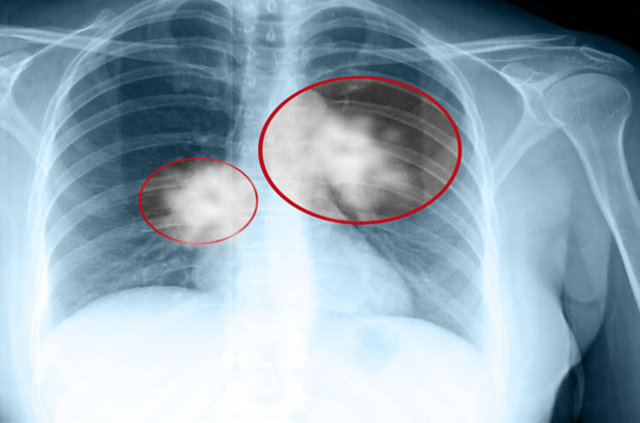

Akciğerlerin her ikisinin ya da birinin dokusunda, anormal hücrelerin kontrolsüz büyümeleri ve çoğalması ile gelişen kötü huylu tümörler, akciğer kanseri tablosunu ortaya çıkarır. Akciğer kanserinde yaş önemli bir faktördür.

Yaş ilerledikçe görülme sıklığı artar. Akciğer kanseri, 45 yaş altında nadiren ortaya çıkabilirken, genellikle 50-70 yaşlarında tanı konulur. Akciğer kanserinin kadınlarda görülme sıklığı ise giderek artar bir konumda...

ERKEN EVREDE BAŞARI İLE TEDAVİ EDİLİYOR

Akciğer kanserinin belirtileriyle karşılaşıldığında mutlaka doktora başvurulmalıdır. Ayrıntılı muayene, aile öyküsünün alınması ve uygun tetkiklerle tanı konulabilir. Akciğer kanseri erken evrelerde tespit edildiğinde başarıyla tedavi edilebiliyor.

15

Akciğer kanserinde tedavi şekli; kanserin tipi, tümörün büyüklüğü, yerleşimi, yaygınlığı ve hastanın genel durumuna göre belirlenir. Günümüzde modern tedavi yöntemleri sayesinde hastaların yaşam kalitesi ve süresi artmış durumdadır.